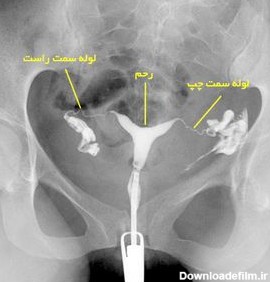

عکس رنگی از رحم سپتوم دار

عکس رنگی رحم سپتوم دار

عکس رنگی رحم چیست؟